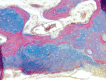

Otosclerosis is a bone condition affecting the stapes bone within the otic capsule, and its exact cause is still unknown. It is characterized by a lack of proper remodeling of newly formed vascular and woven bone, leading to the development of abnormal osteons and the formation of sclerotic bone. Bilateral otosclerosis is seen in 80% of patients and 60% of otosclerosis patients have a family history of the condition. The etiology of this disease is still unknown, there are lots of theories to explain it. The histopathological (HP) studies of otosclerosis showed that osteoblasts, osteoclasts, vascular proliferation, fibroblasts, and histiocytes were observed in the stapes footplate. The onset of the symptoms occurs by the early third decade of life, usually it doesn't start later. In otosclerosis, the energy exerted by sound at the level of the tympanic membrane is reduced in the inner ear due to the fixation and rigidity of the ossicular chain, leading to hearing loss, especially for low frequencies. The primary clinical symptom of otosclerosis is conductive hearing loss but it is important to note that sensorineural hearing loss and mixed hearing loss can also occur as secondary symptoms of the condition. Another symptom present in patients with otosclerosis is tinnitus. The paper carried out a retrospective study of 70 patients diagnosed with otosclerosis in the Department of Otorhinolaryngology of Emergency City Hospital, Timişoara, Romania, between January 2021 to December 2022. Tissue fragments were processed at Service of Pathology by standard Hematoxylin-Eosin staining. The HP diagnosis was completed using Masson's trichrome staining, Giemsa histochemical staining, and immunohistochemical (IHC) reactions with anti-cluster of differentiation (CD)20, anti-CD3, anti-CD4, anti-CD8, anti-CD34, and anti-CD31 antibodies. The microscopic examination showed a chronic diffuse inflammatory infiltrate that consisted predominantly of mature T-lymphocytes, immunohistochemically positive for CD3, CD4 and CD8. There were also present rare CD20-positive B-lymphocytes. Among the lymphocytes, relatively numerous mast cells were identified, highlighted histochemically by the Giemsa staining. They had numerous purple-violet intracytoplasmic granules. In the connective tissue support, a relatively rich vascular network was identified, consisting of hyperemic capillaries, highlighted immunohistochemically with anti-CD31 and anti-CD34 antibodies. Bone tissues trabeculae showed extensive areas of fibrosis. The collagen fibers were highlighted by Masson's trichrome staining, being stained in green, blue, or bluish green.